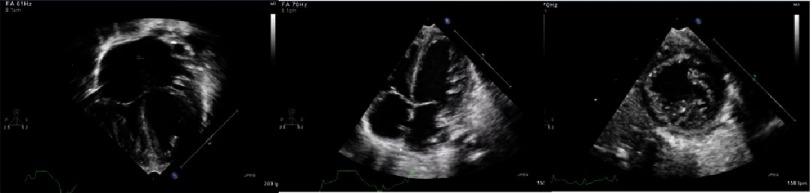

Neuromuscular diseases with hypertrophic cardiomyopathy.

Glob Cardiol Sci Pract. 2018 Aug 12;2018(3):27. doi: 10.21542/gcsp.2018.27.